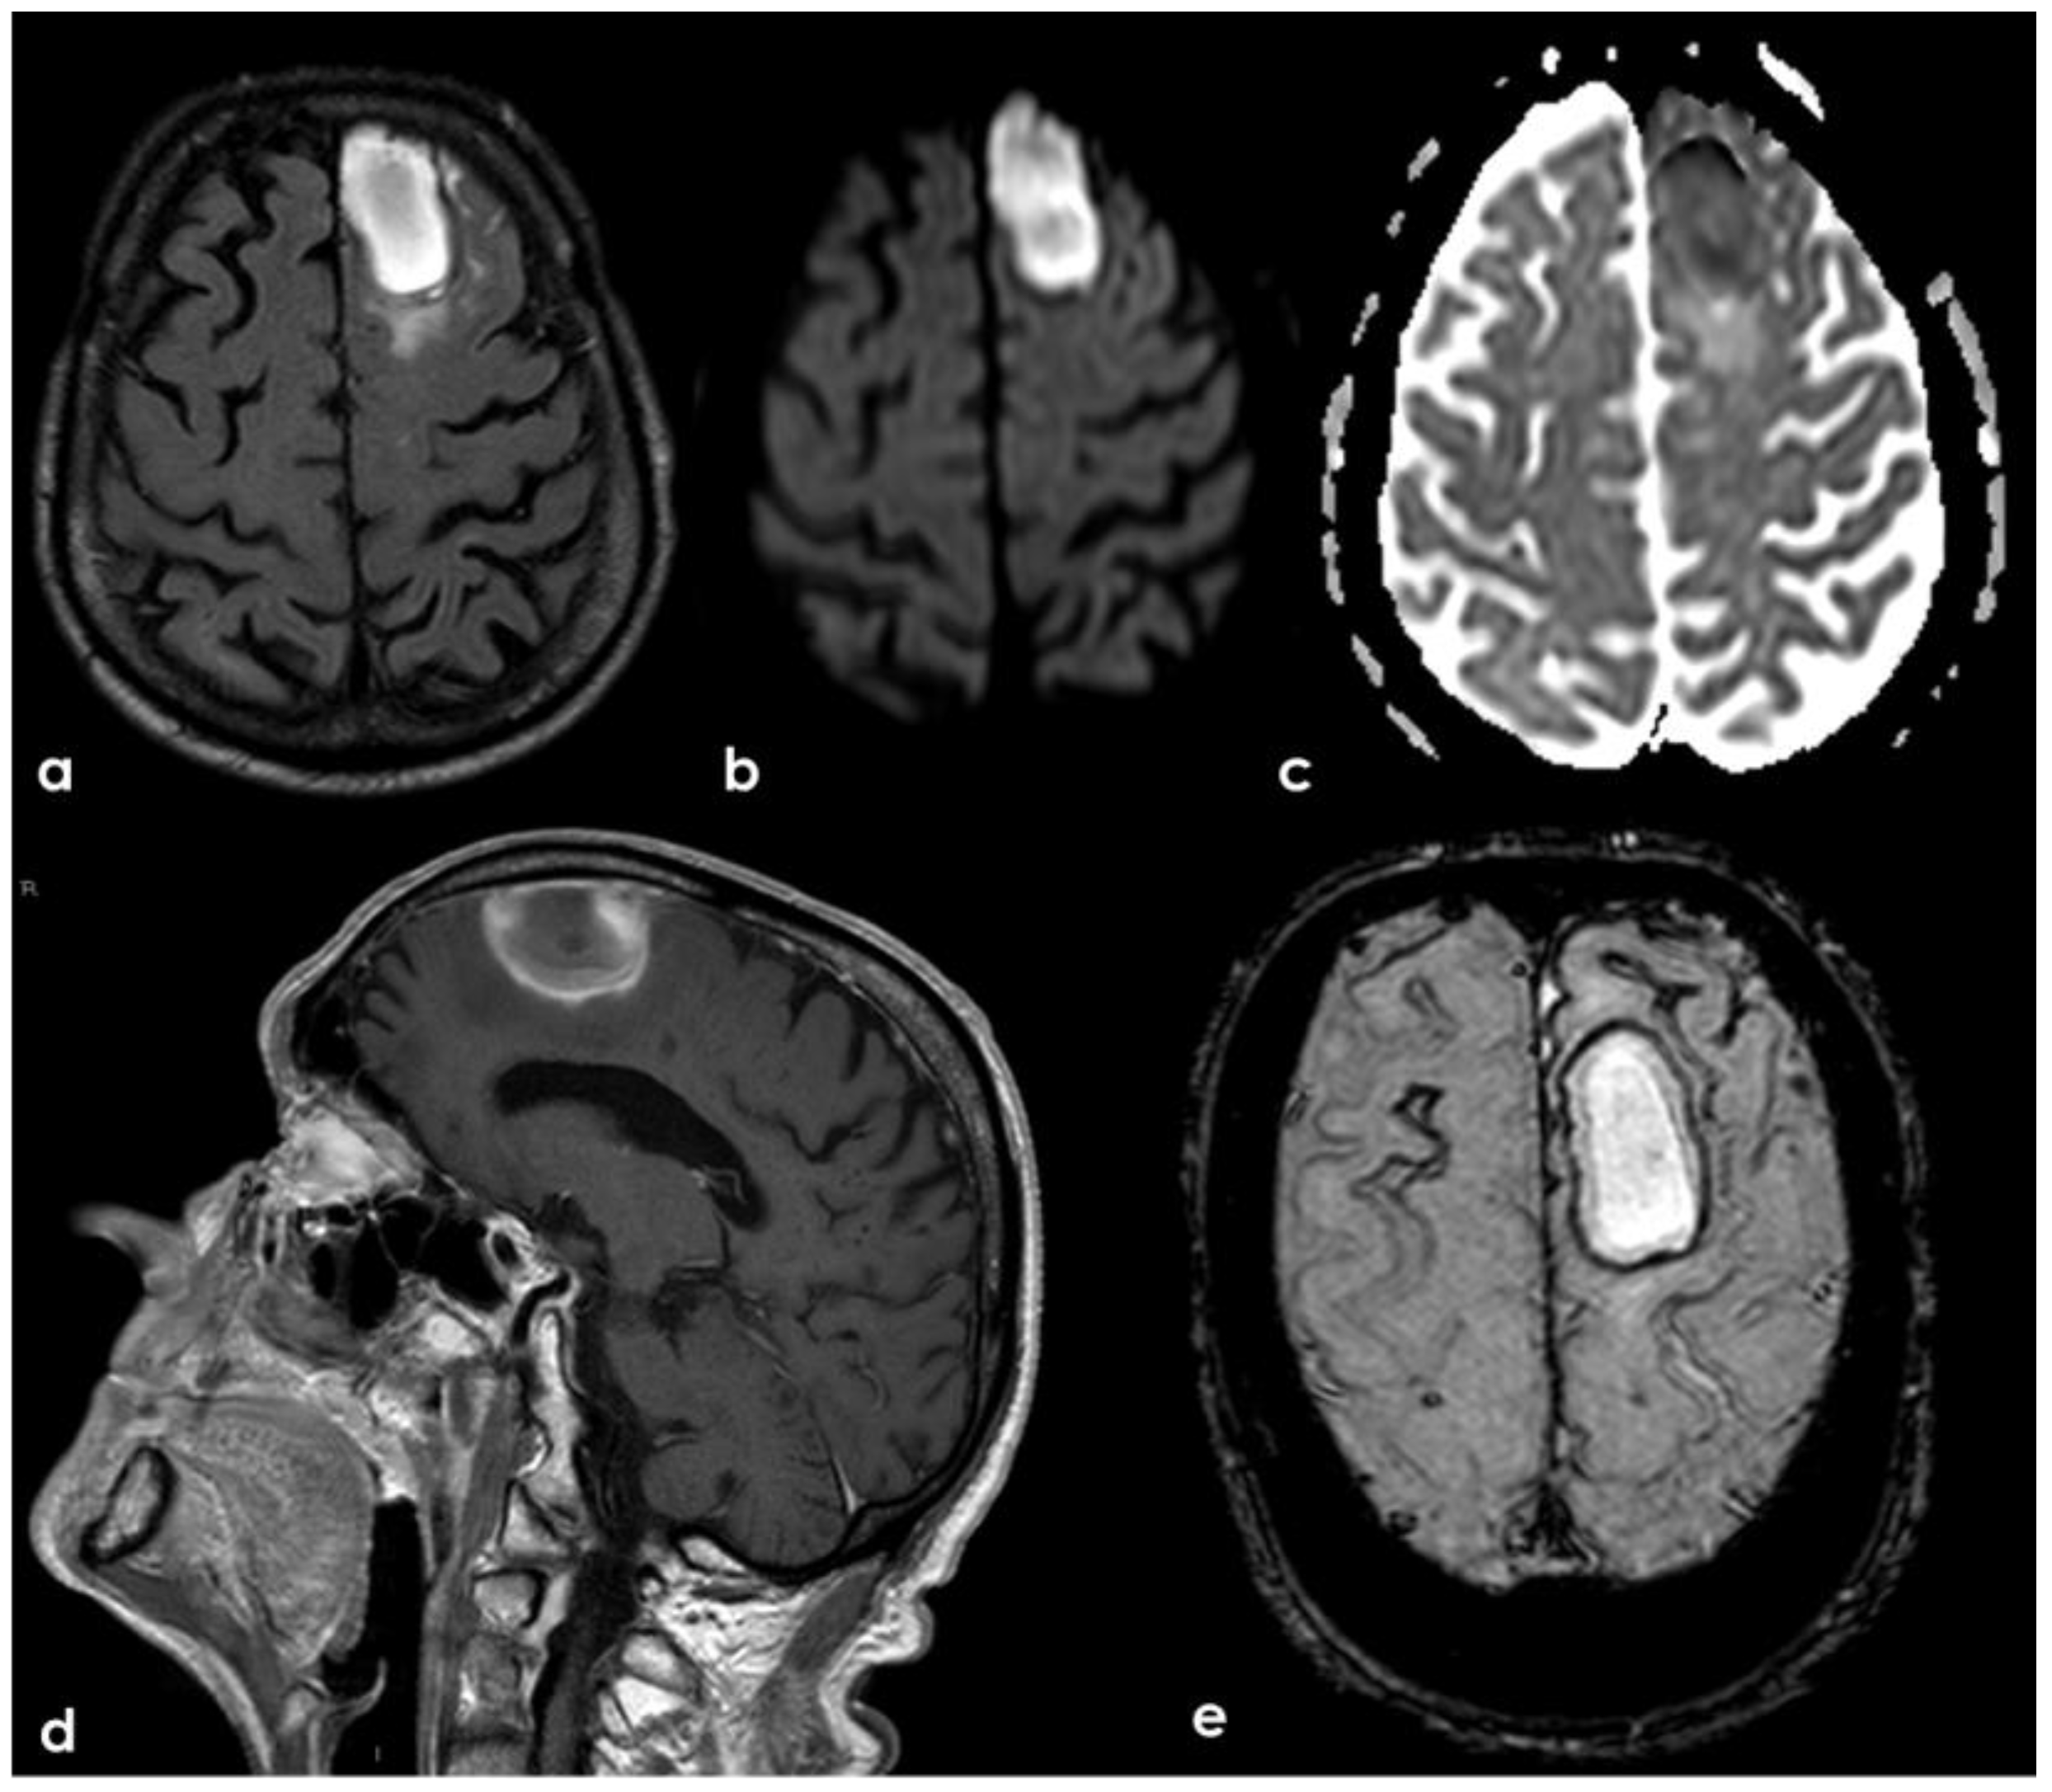

3. May 2014: CAA-Related Inflammation